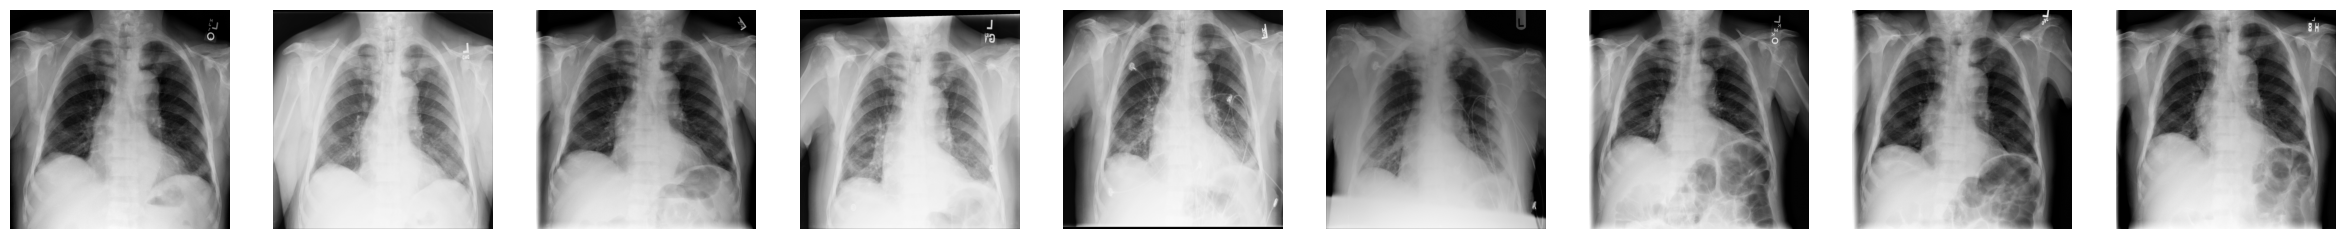

在下一个例子中,您将使用9张来自ChestX-ray8数据集的1024x1024像素的X光图像,这些图像已从数据集中某个文件中下载并解压。它们编号从...000.png到...008.png,我们假设它们属于同一位患者。

1. 导入NumPy,读入每张X光片,并创建一个三维数组,其中第一个维度对应于图像编号

import numpy as np

num_imgs = 9

combined_xray_images_1 = np.array(

[imageio.v3.imread(os.path.join(DIR, f"00000011_00{i}.png")) for i in range(num_imgs)]

)2. 检查包含9张堆叠图像的新X光图像数组的形状

combined_xray_images_1.shape(9, 1024, 1024)请注意,第一个维度的形状与num_imgs匹配,因此combined_xray_images_1数组可以被解释为2D图像的堆栈。

3. 您现在可以使用Matplotlib将每帧并排绘制,以显示“健康进展”

fig, axes = plt.subplots(nrows=1, ncols=num_imgs, figsize=(30, 30))

for img, ax in zip(combined_xray_images_1, axes):

ax.imshow(img, cmap='gray')

ax.axis('off')